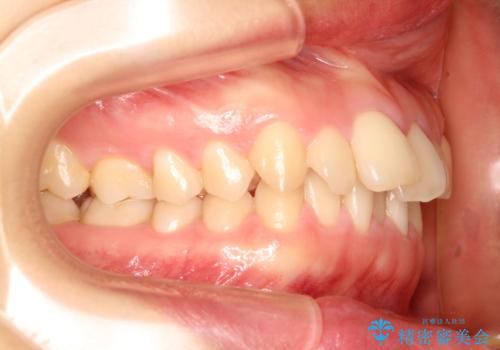

- 出っ歯の改善を希望され来院された患者様です。

初診時の歯並びの状態としては、上下とも前歯部の中等度のがたつきがあり、その他に奥歯の噛み合わせのズレや、口元の突出感も認められました。

奥歯の嚙み合わせのズレを改善するにあたり、カリエールディスタライザーという装置を併用することで治療期間の短縮を図りました。